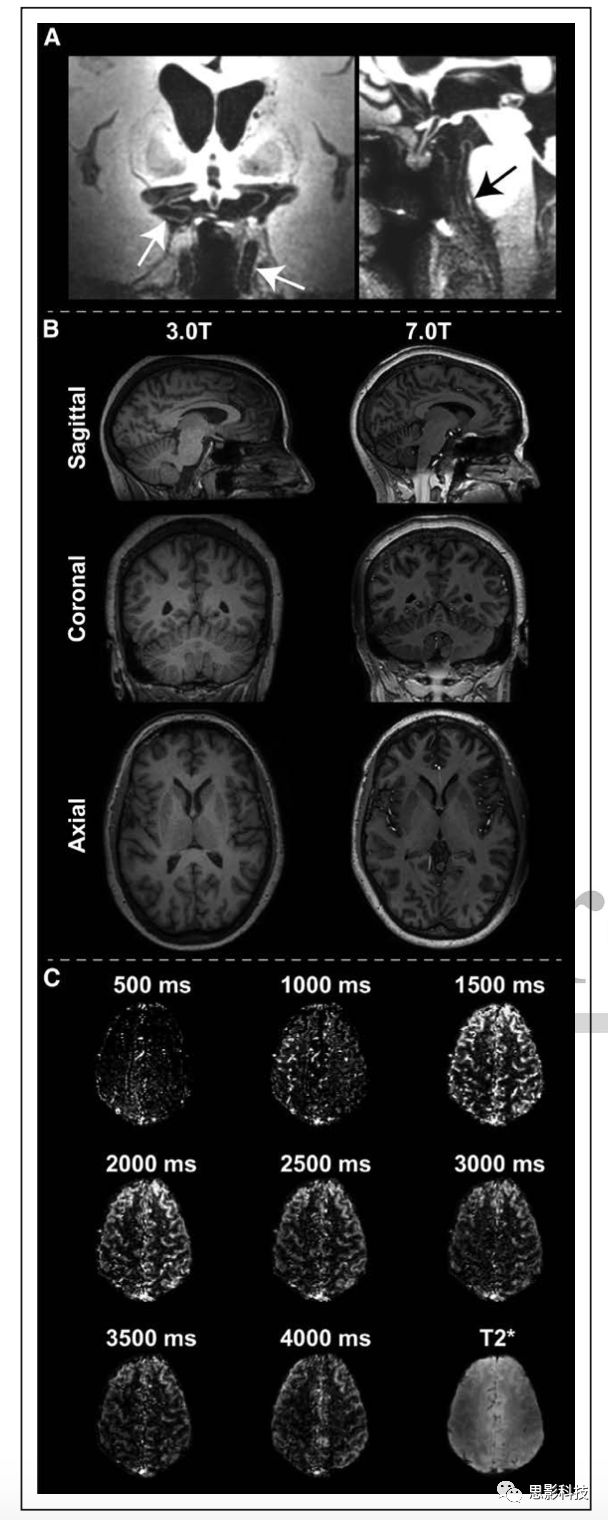

4高場解剖像和血流動(dòng)力學(xué)成像。

A 7.0T血管壁成像顯示顱內(nèi)血管壁節(jié)段(白色箭頭)和基底動(dòng)脈病變(黑色箭頭)

B同一志愿者在3.0T(1mm)7.0T(0.7 mm)條件下,常規(guī)掃描時(shí)間為5min,進(jìn)行T1WI掃描。

C 7.0T,不同的標(biāo)記后延遲時(shí)間的ASL圖像,展現(xiàn)了長到達(dá)時(shí)間(3000-4000ms)定量腦血流量的潛力,這在中風(fēng)中比較常見。圖來自一名成年人。

現(xiàn)使用的磁共振大多數(shù)為1.5T-3.0T,然而,美國食品和藥物管理局(FDA)最近批準(zhǔn)了將7.0T磁共振投入臨床使用,這可能為下一個(gè)十年提供新的研究方向。信噪比隨磁場強(qiáng)度線性增加,因此,理論上,達(dá)到3T掃描的相同空間分辨率,7.0T用不到一半的時(shí)間即可完成。這對解剖結(jié)構(gòu)較小且時(shí)間依從性有問題的未用鎮(zhèn)靜劑的兒科病例很有幫助。且7T還有額外優(yōu)點(diǎn),在3T磁共振中化學(xué)交換飽和轉(zhuǎn)移、BOLDASL等方法存在的問題,如化學(xué)位移離散度的增加,血管內(nèi)相對于血管外的液體T2*信號降低,血液T1值延長,在7T中會得到改善(圖4)。在實(shí)踐中,優(yōu)點(diǎn)也包括高空間分辨率,精確定位BOLD中功能區(qū)域,允許ASL更長的標(biāo)記延遲時(shí)間。但7.0T的也存在很多技術(shù)難題,包括所需的發(fā)射場不能保證在目前安全范圍內(nèi)獲得,主磁場和發(fā)射場的不均勻性,植入物發(fā)熱問題,有限的線圈覆蓋范圍問題以及7.0T系統(tǒng)的可訪問性有限。7.0T磁共振成像臨床相關(guān)應(yīng)用的綜述。doi: 10.1016/j.ejrad.2011.07.007